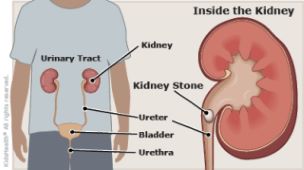

Kidney Stones can lead to further complication in future if you don’t treat it now. It causes blockage by clogging your kidneys with urine. In such cases, Acute Urinary Retention can happen.

It may even develop into Chronic Kidney Disease, Kidney Damage or Infection, Bladder Damage, and Bladder Stones

In time past, the only option for people with Kidney Stone was pain surgery with different methods (shock wave lithotripsy, ureteroscopy and percutaneous nephrolithotomy), this procedure involves “shock waves to break up the kidney stones” or”tube inserted directly into your kidney to remove the stones”.